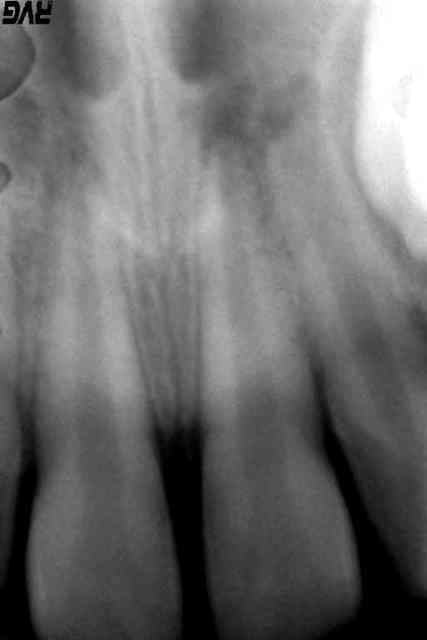

74_image_inter_radic_prbqju.jpg